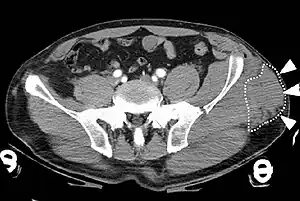

| A Morel-Lavallée lesion is a closed traumatic soft-tissue degloving injury, caused by separation of the hypodermis from the underlying fascia.[1] It most frequently occurs in the peritrochanteric region along the proximal lateral thigh,[1] such as in this CT scan. | |